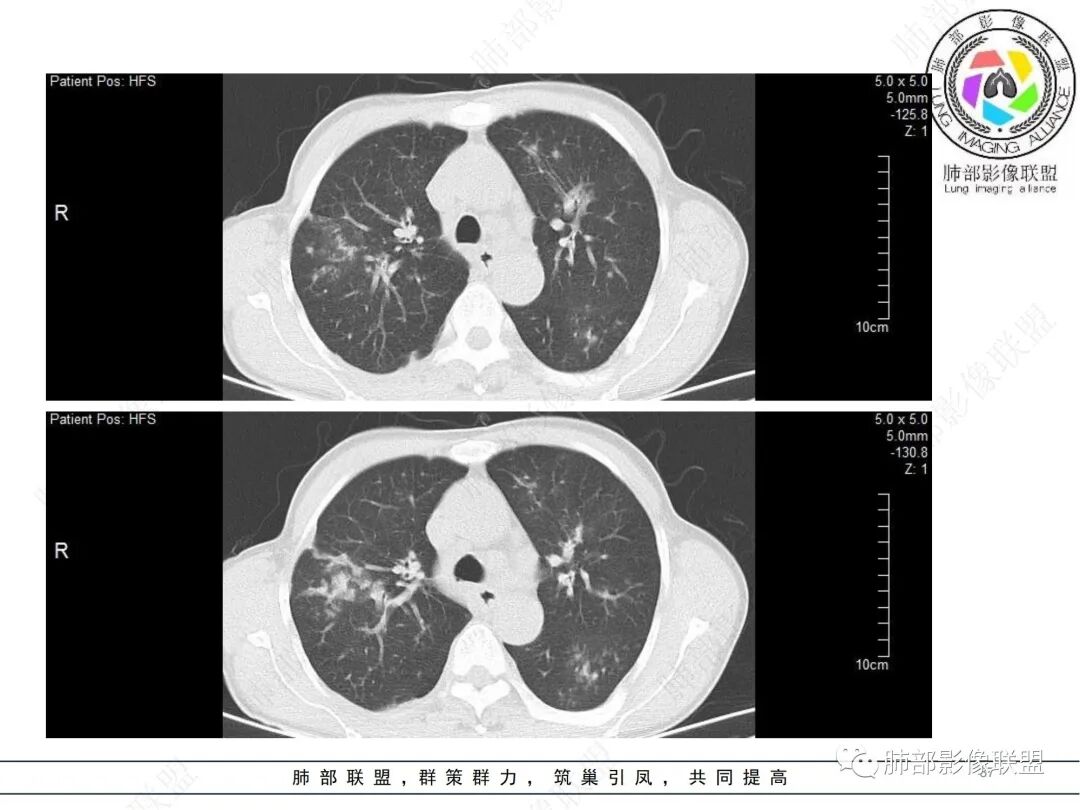

58岁男性,咳嗽胸闷3天,咳较多褐粘液痰,无发热。有2型糖尿病病史。白细胞与中性粒细胞升高。CRP升高。鳞状上皮细胞癌抗原轻度升高。结核T细胞免疫斑点实性阳性。肺炎支原体、衣原体IgG轻度升高。支气管镜显示支气管炎性改变、右肺下叶背段管腔狭窄。2.影像特点:

2022.6.24CT显示两肺弥漫性段、亚段支气管壁增厚(两肺各叶都累及),增厚的支气管壁外可见沿着支气管分布的渗出、实变影。另外远端肺内亦可见多发树芽影、结节影,其边界欠清晰。右肺下叶基底段局部胸膜下亦可见小斑片影,边界不清。2022.6.27CT显示两肺增厚的支气管壁外的渗出实变影明显增多、范围更广。远端肺内病灶亦增多、范围增大。部分位于胸膜下的病灶可见侧向融合趋势。3.病例分析: